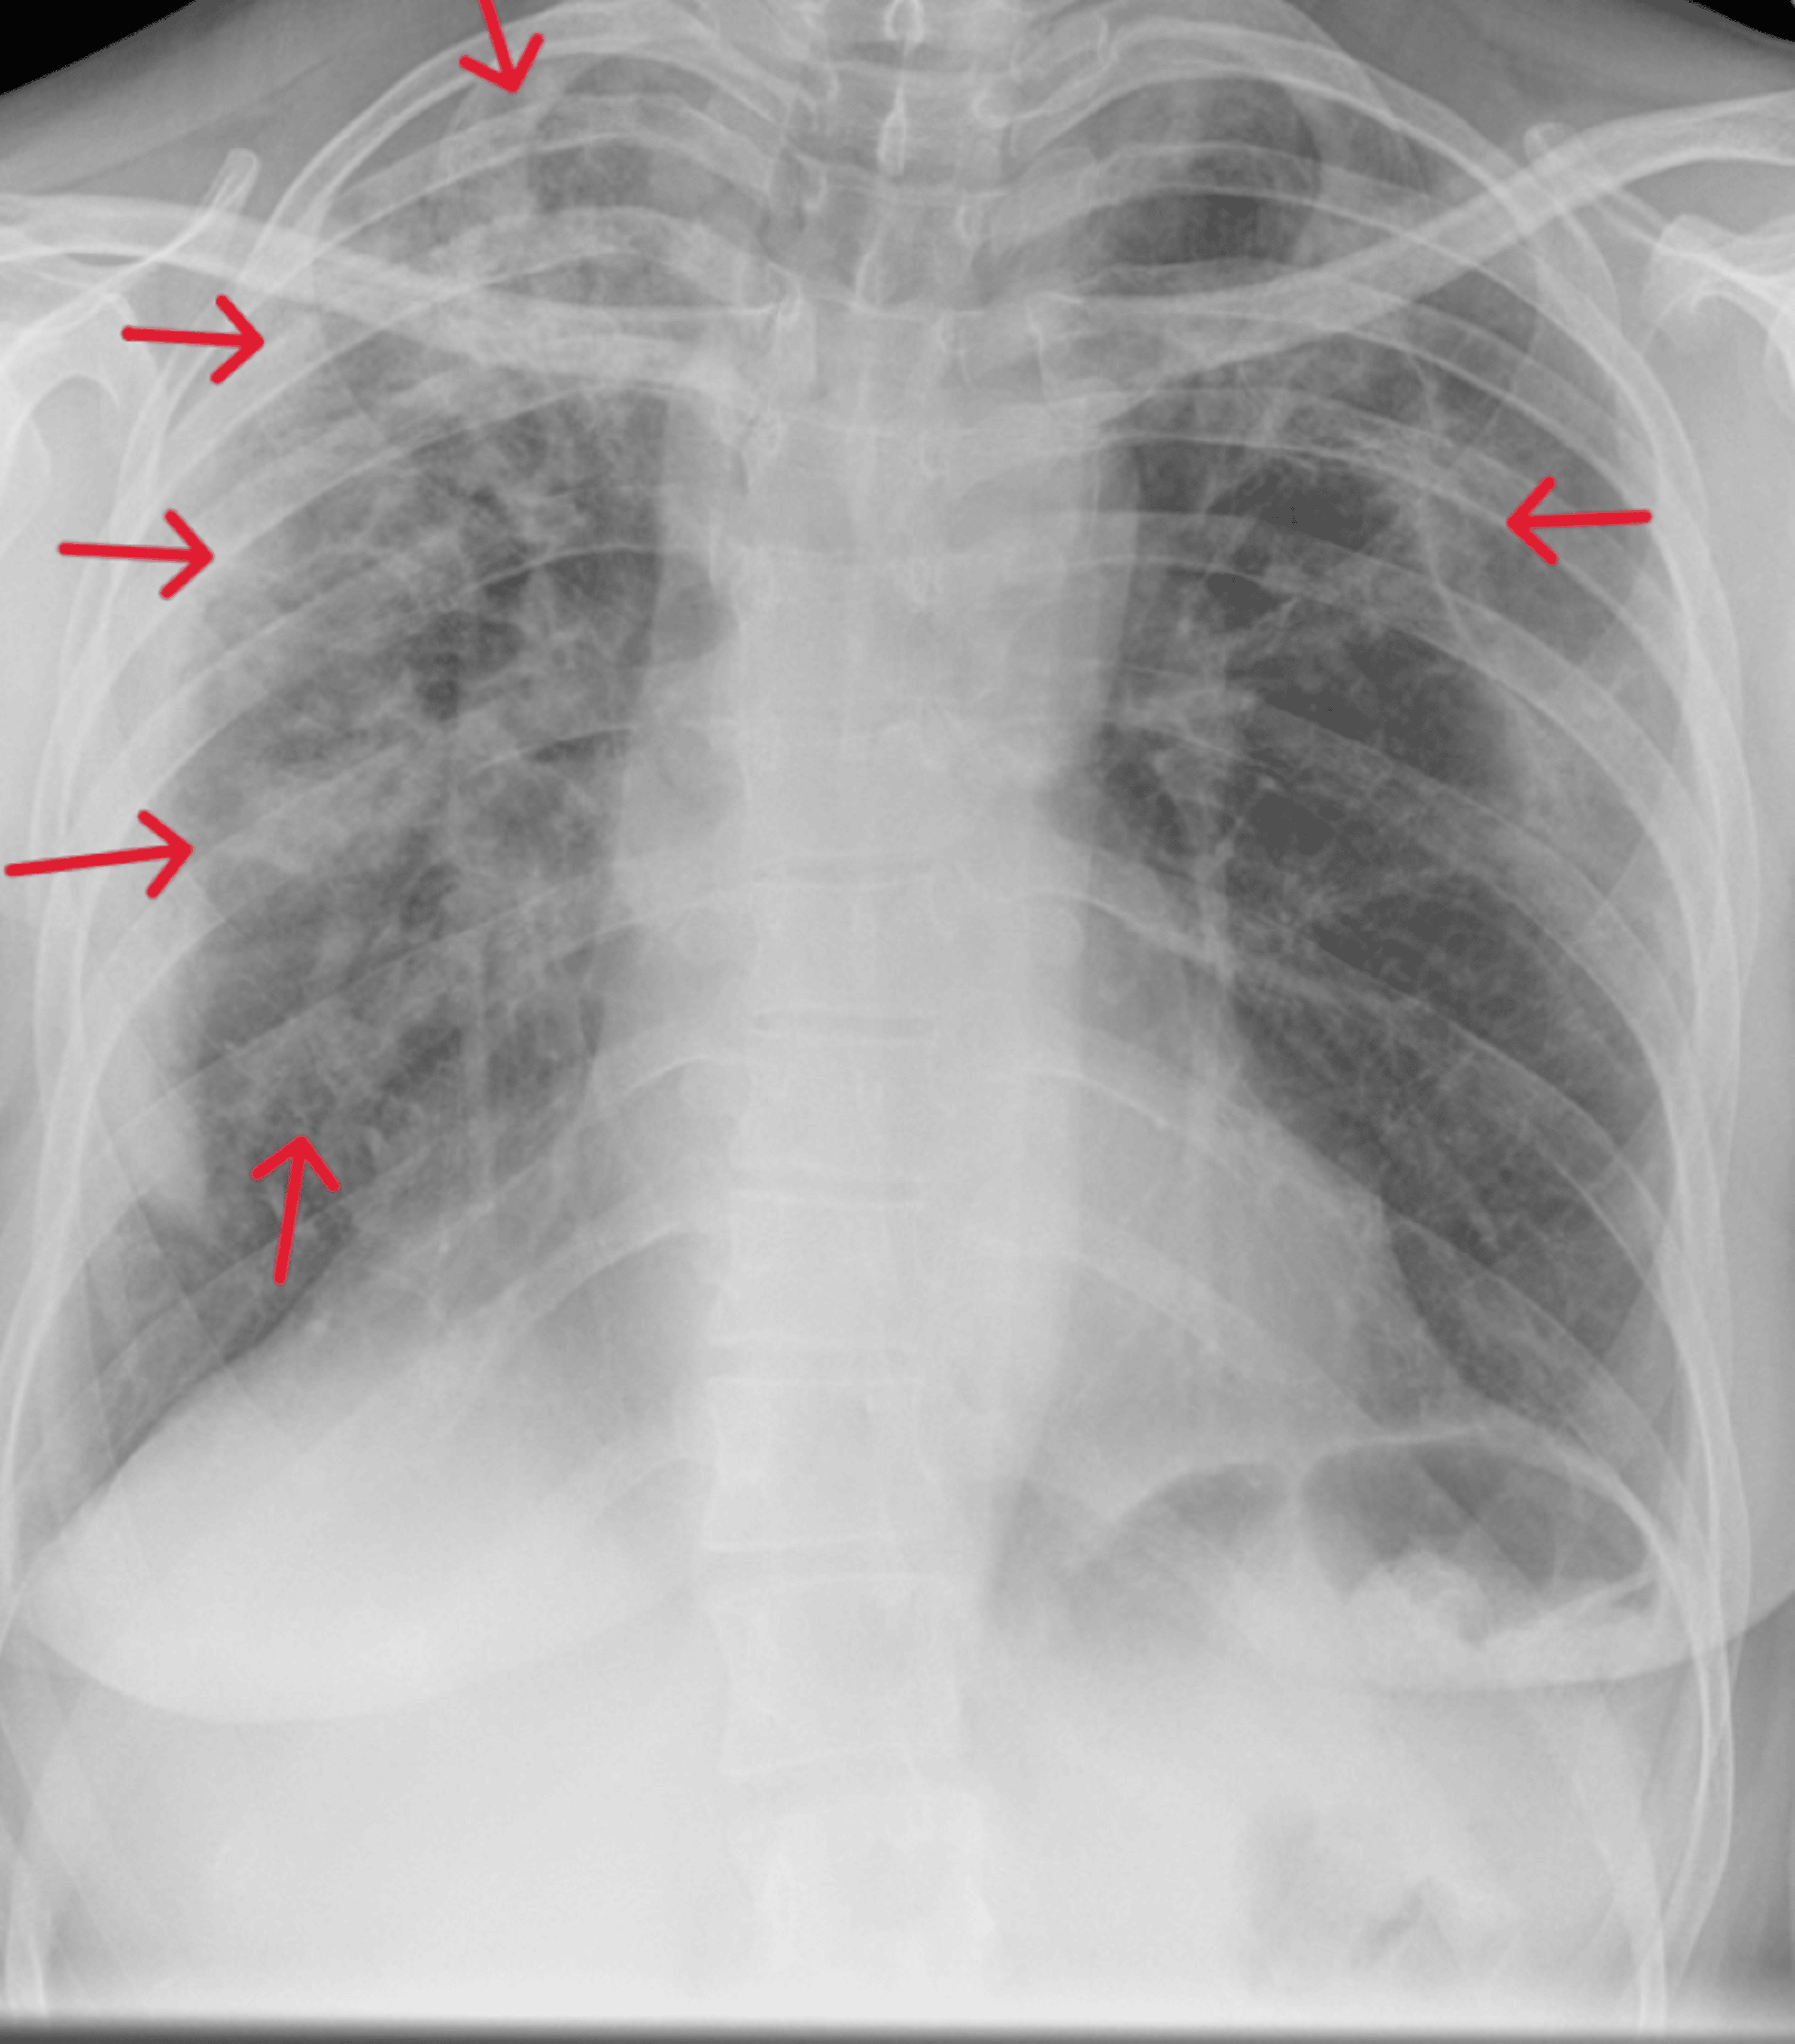

From prepareformedicalexams.blogspot.com

Prepare for Medical Exams A 19yearold boy has a history of repeated Do All Chest Infections Show Up On Xray Blood tests and phlegm (sputum). The interpretation of a chest film. Imaging plays an integral role in the diagnosis and management of suspected pulmonary infections and may reveal useful signs on chest radiographs and ct scans. In fact every radiologst should be an expert in chest film reading. Chest x‐rays in acute chest infections. Acute chest infections (lower respiratory tract. Do All Chest Infections Show Up On Xray.